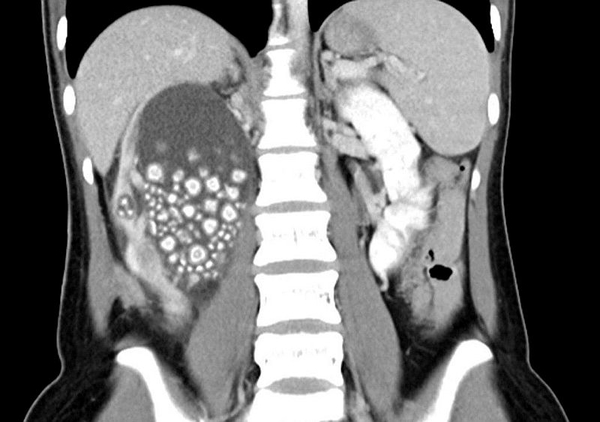

Öte yandan, Chi Mei Hastanesi Ürologu Lin Tsai-yang, Tayvan’daki erkeklerin yüzde 14,9’unda, kadınların ise yüzde 4,3’ünde böbrek taşı oluşma ihtimali bulunduğunu kaydetti.